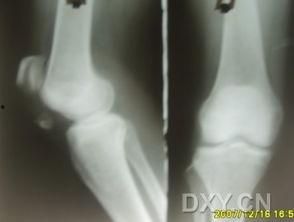

想象当你的骨头因为骨折而断裂时,医生会用克氏针将断裂的骨头固定在一起,让它们慢慢愈合。这个过程听起来是不是有点神奇?其实,这就是克氏针的魔力所在。

2. 手术过程:手术过程中,医生会在患者的骨折部位打一个小孔,然后将克氏针从孔中穿入,穿过骨折的骨头,最后固定在皮肤外。这个过程听起来有点复杂,但医生们却游刃有余。